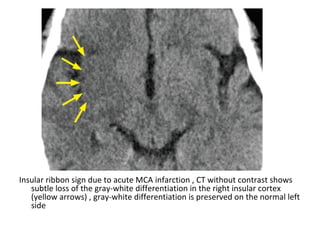

3-The (insular ribbon sign) is a finding of early

MCA infarction describes the loss of gray-

white matter differentiation in the insula , the

normal striated appearance of this area is

replaced by a swollen homogeneous area of

low attenuation

Insular ribbon sign due to acute MCA infarction , CT without contrast shows

subtle loss of the gray-white differentiation in the right insular cortex

(yellow arrows) , gray-white differentiation is preserved on the normal left

side

-Insular ribbon sign ,

this refers to

hypodensity and

swelling of the insular

cortex , it is a very

indicative and subtle

early CT-sign of

infarction in the

territory of the MCA

-This region is very

sensitive to ischaemia

following MCA

occlusion than other

portions of the MCA

territory because it

has the least potential

for collateral supply

from the ACA & PCA